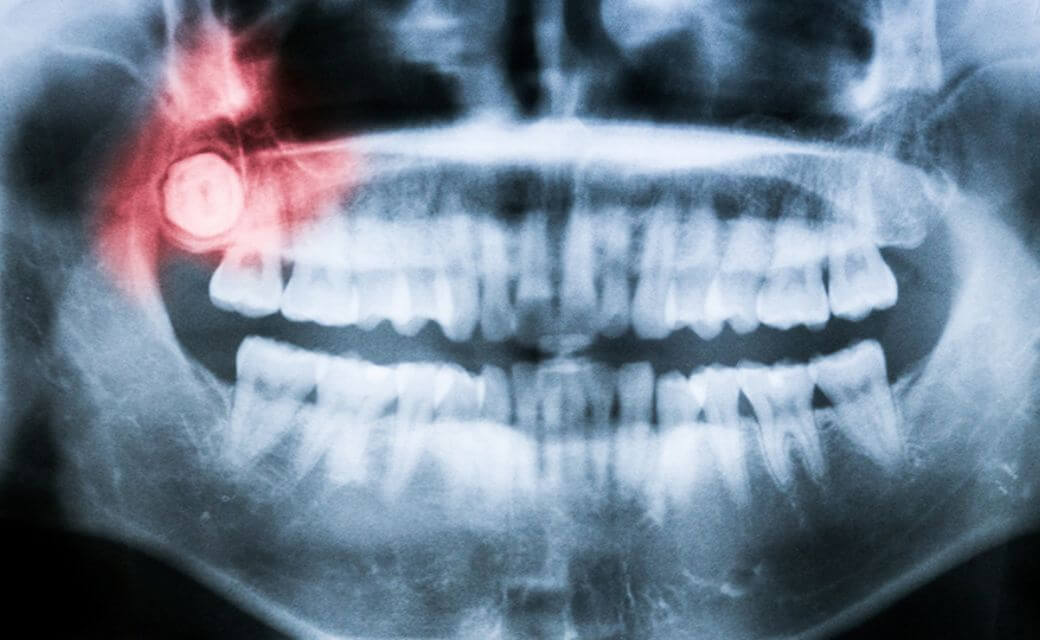

朝日大学口腔外科様は、歯科関係において一般的な歯の治療の他、インプラントや、咀嚼機能に関わる治療、がん治療など幅広い分野に実績があります。歯科先生から、ケーススタディの論文の英語化を依頼されます。日本語の原文をもとに英文にしますが、内容に問題点があれば、先生に疑問点について改善点を提案します。また、論文が最終的にアクセプトされるまでの修正についても丁寧に対応しています。